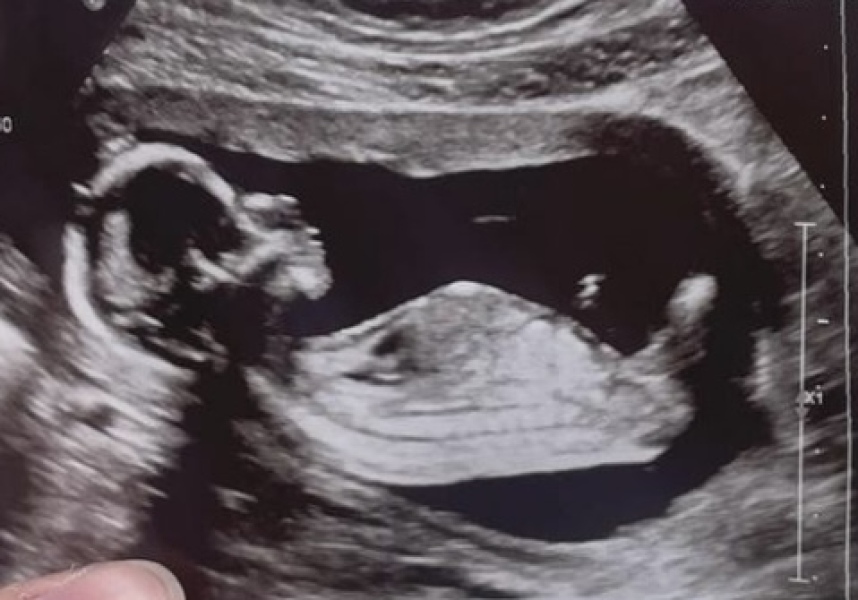

NUB THEORY GUESSES PLEASE?

12 weeks and 1 day at this scan. Thank you!

Just an update to this.. had our scan today and it’s a girl!!!! So shocked I’ve had all boy guesses across several groups so I was convinced it was a little man x